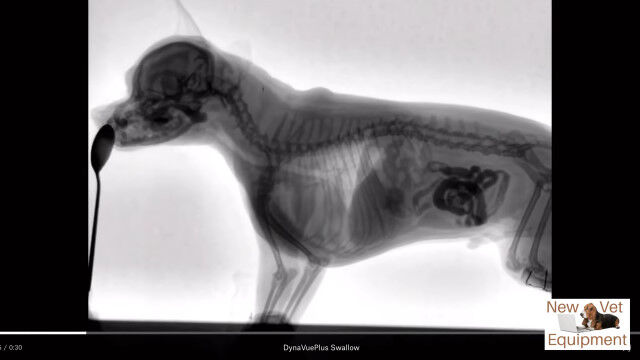

動物用レントゲンシステム、ダイナビューを用いて撮影された、犬がエサを食べる最中の体内の様子。

口から食道を通り、ゆっくり胃袋へ流れ込む様子が動画ではっきり確認できる。

Youtubeの概要欄に記載がなくて分からなかったけど、これ犬種はなんだろうね。

Veterinary Fluoroscopy - Watch the Swallow!